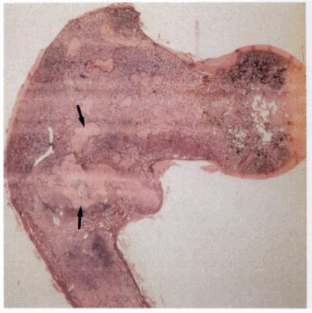

3. Макроскопические и хирургические особенности:

• Фиброзная ткань, имеющая «песчаную» структуру и цвет от желтовато-коричневого до серого

• Вариабельная консистенция, которая зависит от фиброзного и костного компонентов

• Грубоволокнистая костная ткань незрелая, непрочная, склонна к переломам

• Могут присутствовать геморрагические, кистозные изменения

4. Микроскопия:

• Фиброзная строма, обычно бессосудистая, низкая целлюлярность

• Метаплазия костей: костные трабекулы, состоящие из незрелой, грубоволокнистой костной ткани, которые выглядят как фигуры необычной формы, «плавающие» в фиброзной строме

о Похожи на «китайские иероглифы» или «алфавитный суп»